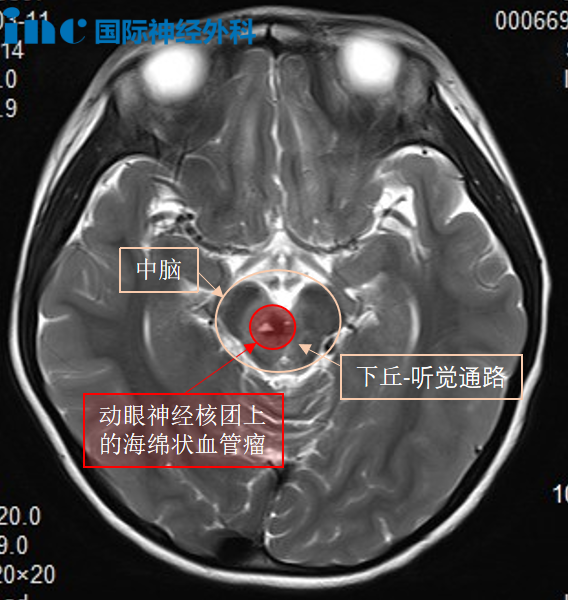

然而,手术的困难还远不止这一点。除开果果年幼,出血风险更难控制的难点外,肿瘤的位置也十分刁钻。肿瘤位于脑干中脑偏右侧,且累及动眼神经核——动眼神经是支配眼肌运动主要的神经,仅有2毫米粗,却与肿瘤粘连紧密。如果手术中动眼神经核被完全损伤,果果的单侧眼睛将不能活动,且永远无法睁开。